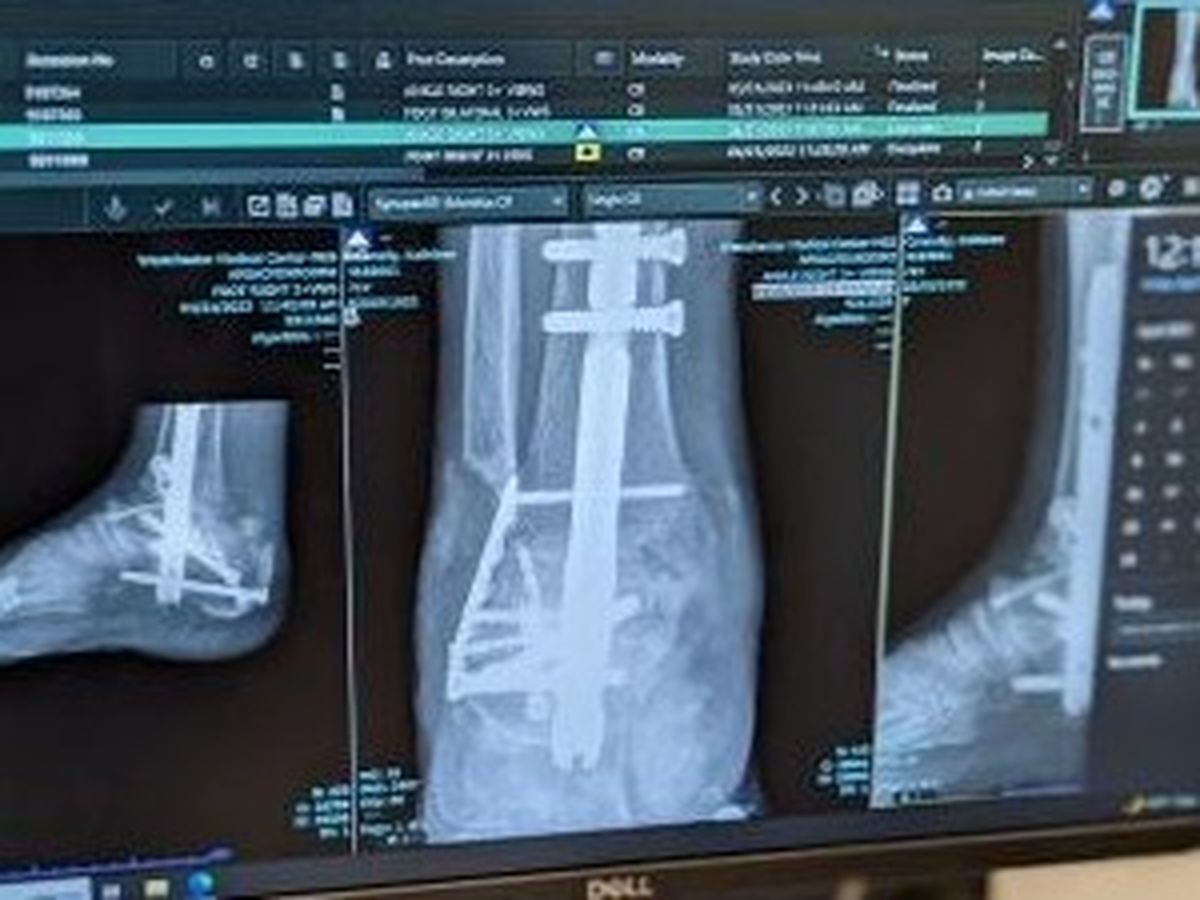

Kathy was pinned in her vehicle and had to be extricated by first responders. She was rushed to the hospital in excruciating pain. Her extent of injuries were, a concussion, a broken left wrist, a fractured left foot, fractured back injuries, a right foot shattered talus bone. Kathy was immediately sent into surgery to repair her left wrist. Doctors had to piece back her wrist with a plate and screws, and cast that arm. A few days later Kathy underwent another surgery to do major reconstructive surgery to her right foot, and that was put in a cast. Kathy remained in the hospital for a month before entering a rehabilitation center where she would spend 2 months non weight bearing, and another month fighting through the pain and extensive physical therapy.